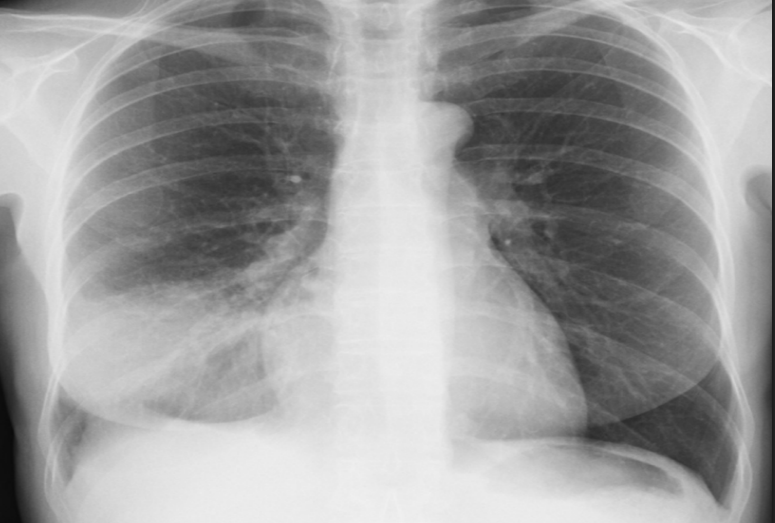

Lung mets (RCC mc cause)

variable in size, well defined, radio-opacities, diffuse, bilateral

Canonball appearance